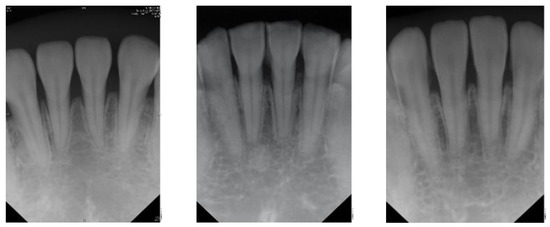

Table 4 shows that the larger the indicators the better is the accuracy. Table 4 also shows that the indicators in the proposed model are larger than that of the previous work in [23]. Consequently, the CNN image identification ability should be excellent especially in clinical medicine thus the need for high-precision judgment to provide better medical quality. The actual application of this technology uses the clinical images of Figure 7 and Figure 8 as the target image for judging the symptoms. After implementing this technology, the results are shown in Table 5 and Table 6.

Figure 8. Outer example for validation (number 1 to 3 from left to right).

Table 6. Result after judgement for Figure 8 sample image.

Figure 8

Number

Clinical DataThis Study

1Normal98.5% to be normal

2Apical lesion99.5% to be apical lesion

3Normal97.3% to be normal